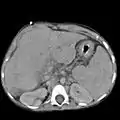

Ultrasound is routinely used in the evaluation of cirrhosis. It may show a small and nodular liver in advanced cirrhosis along with increased echogenicity with irregular appearing areas. Other liver findings suggestive of cirrhosis in imaging are an enlarged caudate lobe, widening of the fissures and enlargement of the spleen. An enlarged spleen (splenomegaly), which normally measures less than 11–12 cm in adults, can be seen and may suggest underlying portal hypertension. Ultrasound may also screen for hepatocellular carcinoma, portal hypertension, and Budd-Chiari syndrome (by assessing flow in the hepatic vein). An increased portal vein pulsatility is an indicator of cirrhosis, but may also be caused by an increased right atrial pressure.[33] Portal vein pulsatility can be quantified by pulsatility indices (PI), where an index above a certain cutoff indicates pathology:

Other tests performed in particular circumstances include abdominal CT and liver/bile duct MRI (MRCP).

Liver cirrhosis as seen on a CT of the abdomen in transverse orientation caudate lobe hypertrophy in ultrasound due to cirrhosis

caudate lobe hypertrophy in ultrasound due to cirrhosis Hepatofugal flow in portal vein in ultrasound